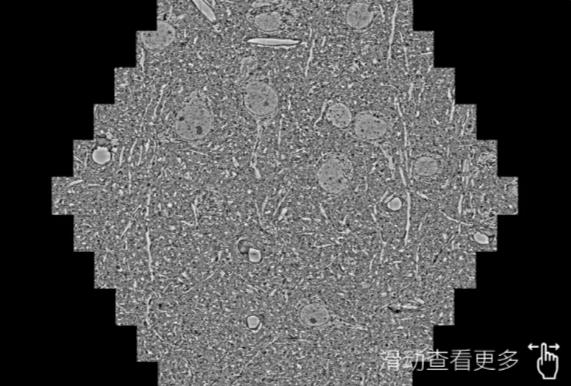

鼠脑切片。左图使用眉山蔡司眉山扫描电镜MultiSEM706对165μmx143pm面积区域成像,耗时仅需1.5秒。右图为鼠脑切片中30μm区域放大效果。样品由芝加哥大学B.Kasthuri提供。

使用蔡司高速眉山扫描电镜MultiSEM对1mm²人脑皮层组织进行高分辨成像,并对其中的各种细胞结构进行三维重构分析。左图展示了2x3mm²组织平面中锥体神经元的三维重构效果。右图显示了局部体积神经元三维重构。图像由哈佛大学chtman实验室提供,渲染图由D. Berger 制作。